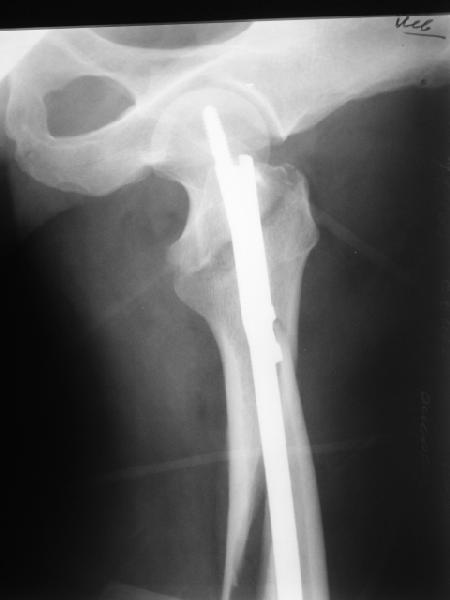

Как раз недавно у меня был примерный случай: больному 36 лет, поступил ночью, травма в результате мотоциклетной аварии, кроме чрезвертельного и спирального перелома левого бедра имеется переломы костей предплечья с этой же стороны. Скелетное вытяжение, а на следующий день больной про оперирован на ортопедическом столе с дистракцией. Чтобы не расколоть чрезвертельный перелом провели временную спицу ближе к переднему кортексу, из малого разреза костодержатель для репозиции, а фиксацию провели антиградным штифтом. Этапы операции на снимках.

Да, сейчас это и у нас самый напрашивающийся выбор. Сделали гвоздем ChM, картинки в приложении.

У молодых реконструкционный гвоздь самое то. При остеопорозе надо что-то помассивнее.